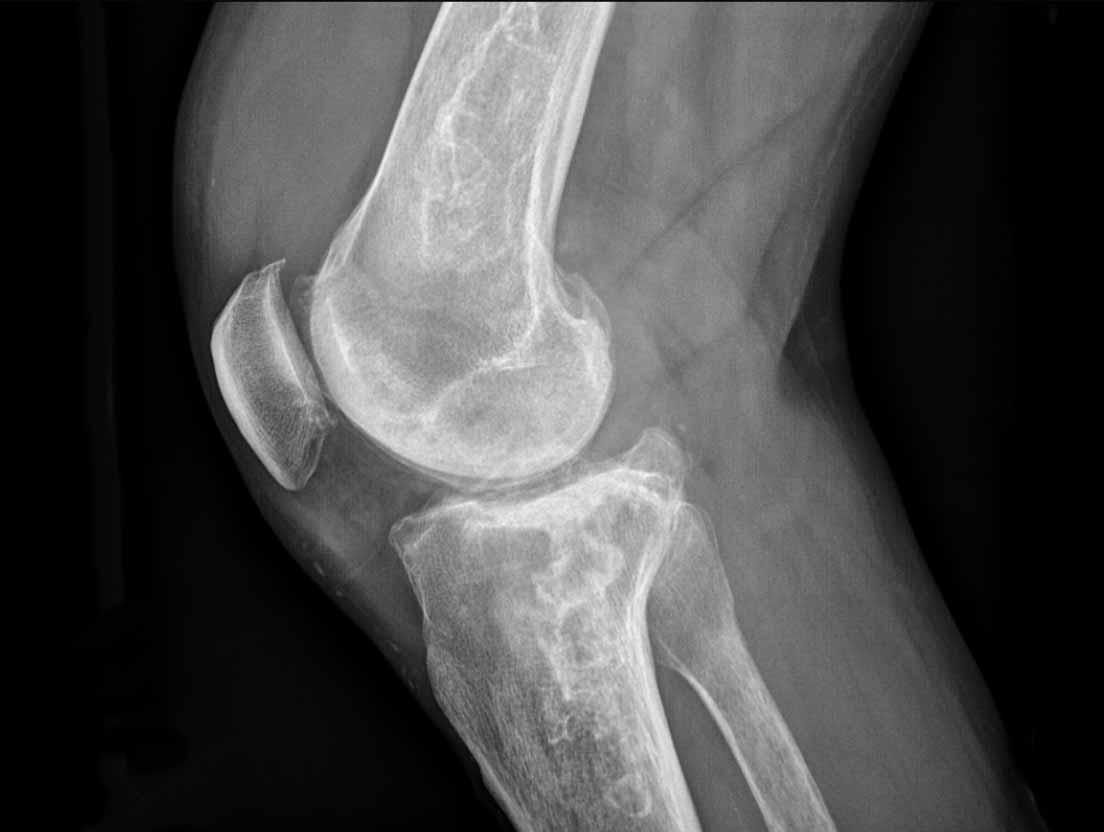

Hình ảnh

Phim X-quang cho thấy nhiều tổn thương xơ cứng dạng rắn bò ở đầu xa xương đùi và đầu gần xương chày, tập trung ở vùng hành xương.

Hình ảnh này điển hình cho nhồi máu xương và xảy ra do sử dụng corticosteroid kéo dài ở bệnh nhân mắc lupus ban đỏ hệ thống (SLE).

Lưu ý sự vắng mặt của các vôi hóa dạng chấm sụn.